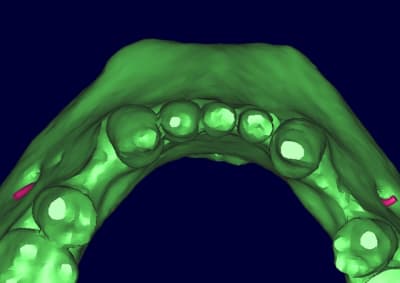

dentiste57 écrivait:

--------------------

> et là ?

> greffe selon ta méthode ?

Cross section dhvkc8 - Eugenol

3d dt3qom - Eugenol

Overview uqcp6u - Eugenol

expansion, c'est plus cool!